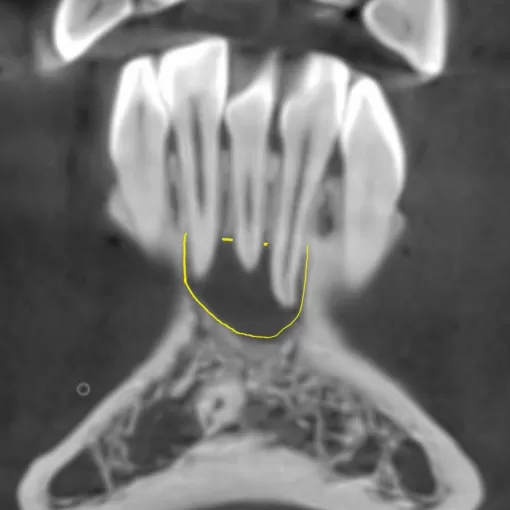

Клинический случай лечения "кисты" зуба 4.7

Стоматолог-терапевт Петрусенко О.А.

Пациент обратился с целью имплантации в области отсутствующего зуба 4.6. Однако после КЛКТ (3Д) исследования был обнаружен воспалительный процесс (киста) в области соседнего зуба 4.7 (рис. 1).